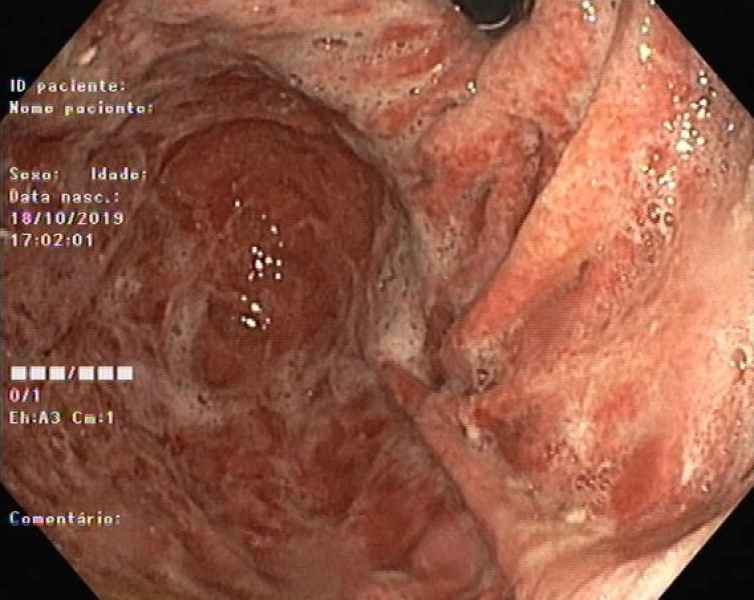

Gastric Crohn's disease